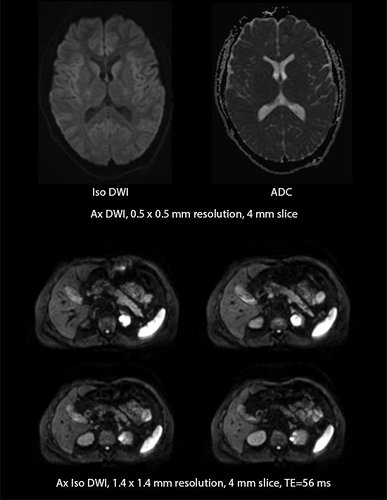

• Optimierung von Diffusionsbildern durch PUREGradienten-Technologie

• MultiBand SPEEDER beschleunigt Aufnahmedauer hochaufgelöster Diffusionsbilder